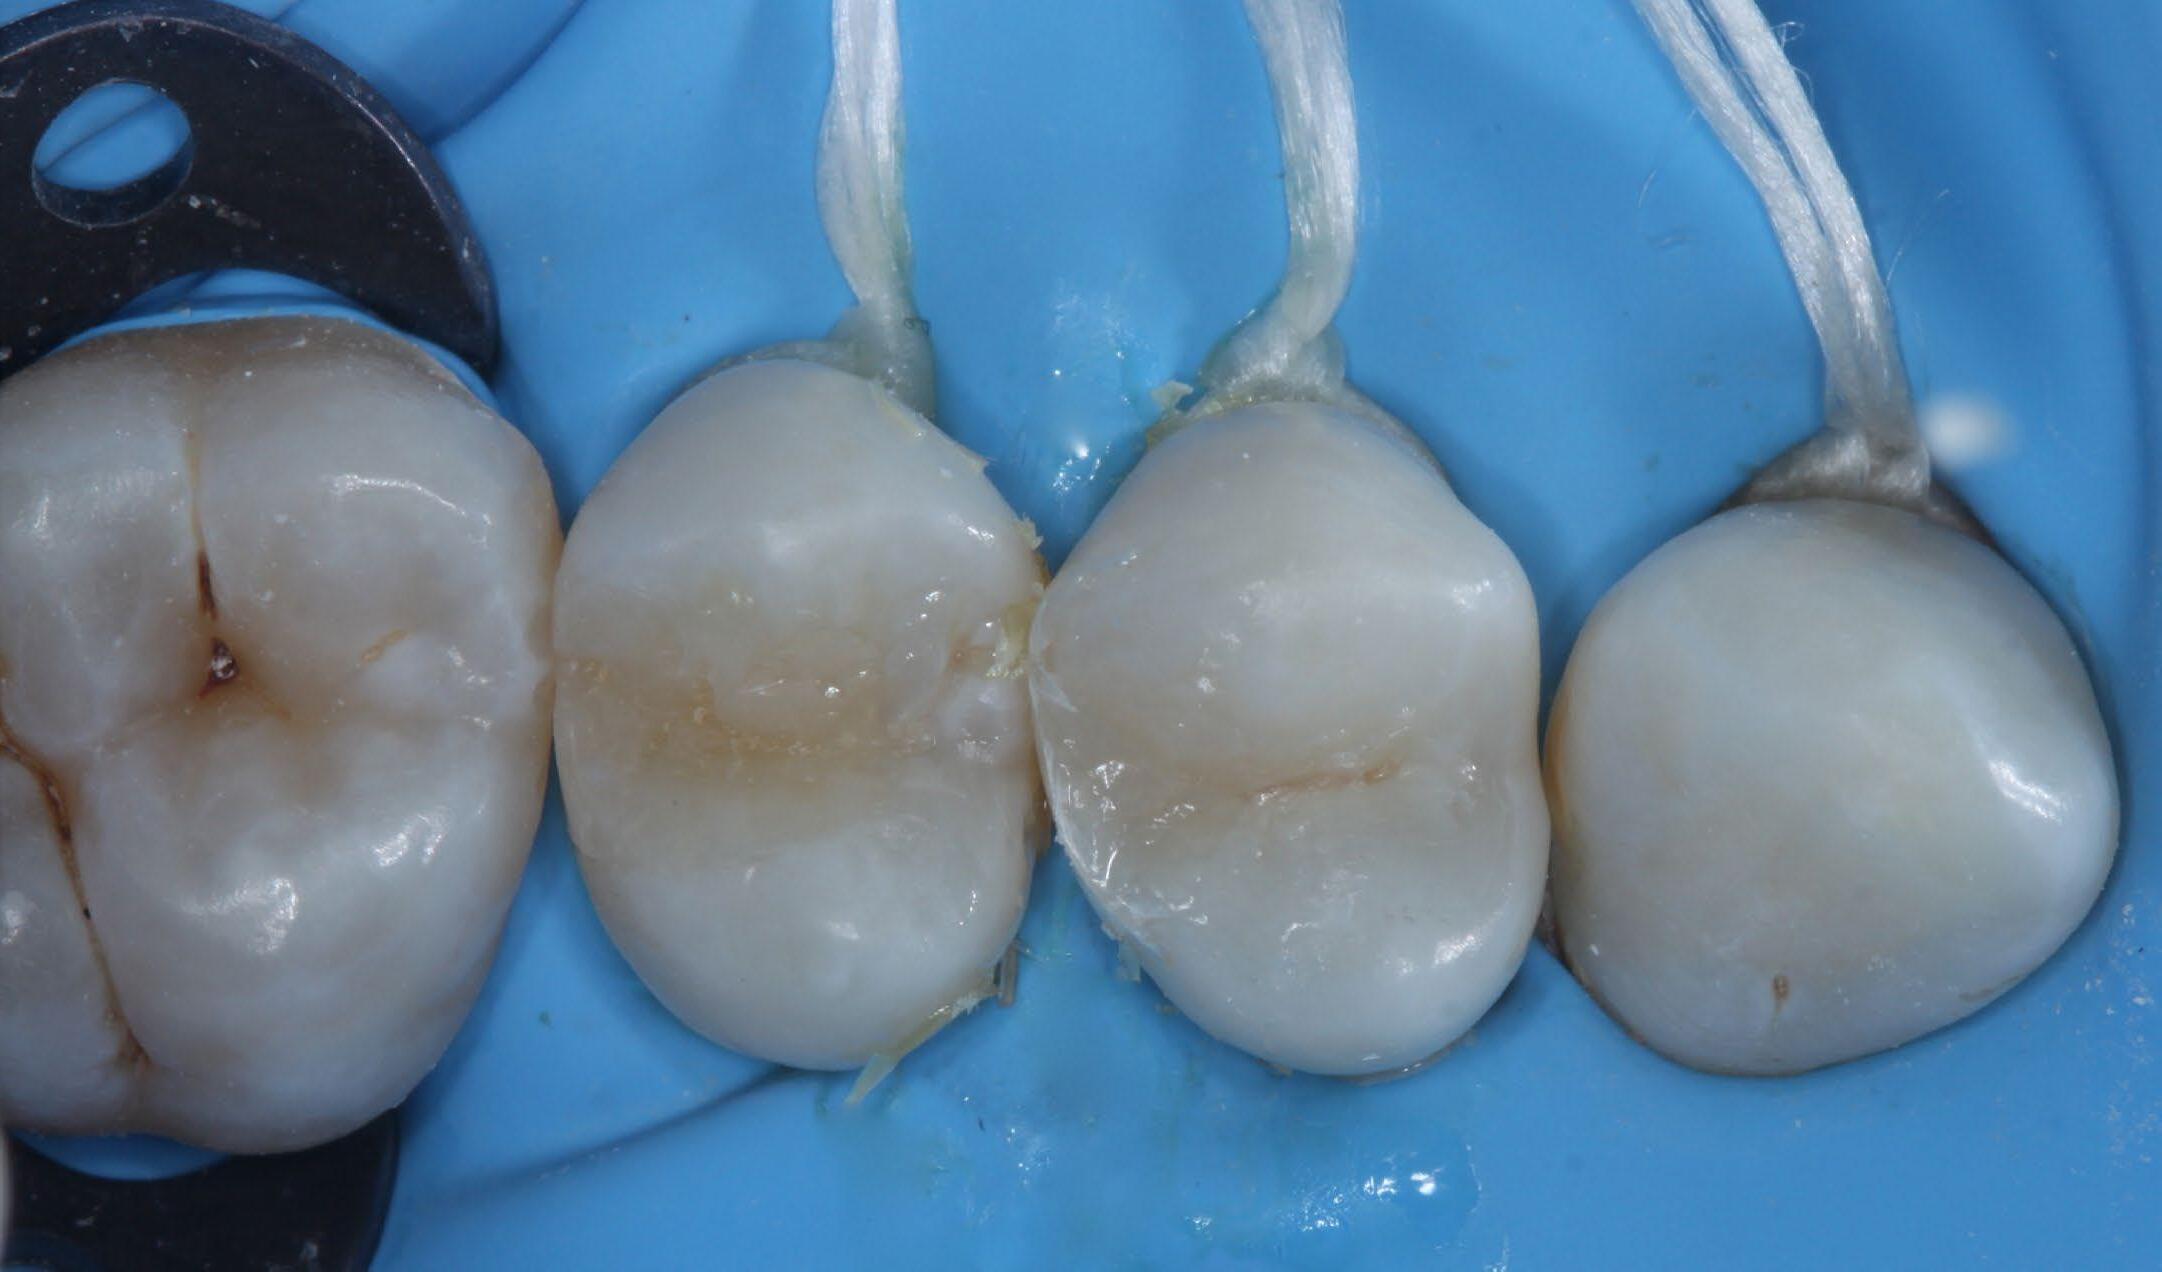

Fig. 1: Initial situation. Fig. 2: X-ray showed hidden caries at the distal side of the upper first pre-molar. Fig. 3: Isolation with rubber dam. Fig. 4: Preparation. Hidden Proximal Caries | Posterior continues next page >>>